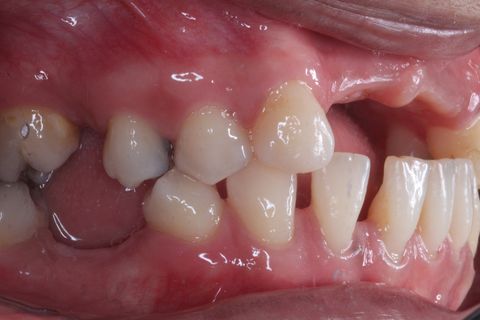

Foto Inicial. Paciente fazendo uso de Prótese Parcial removível.

Foto Perfil (uso de espelho). Lado esquerdo

Foto Perfil (uso de espelho). Lado Direito